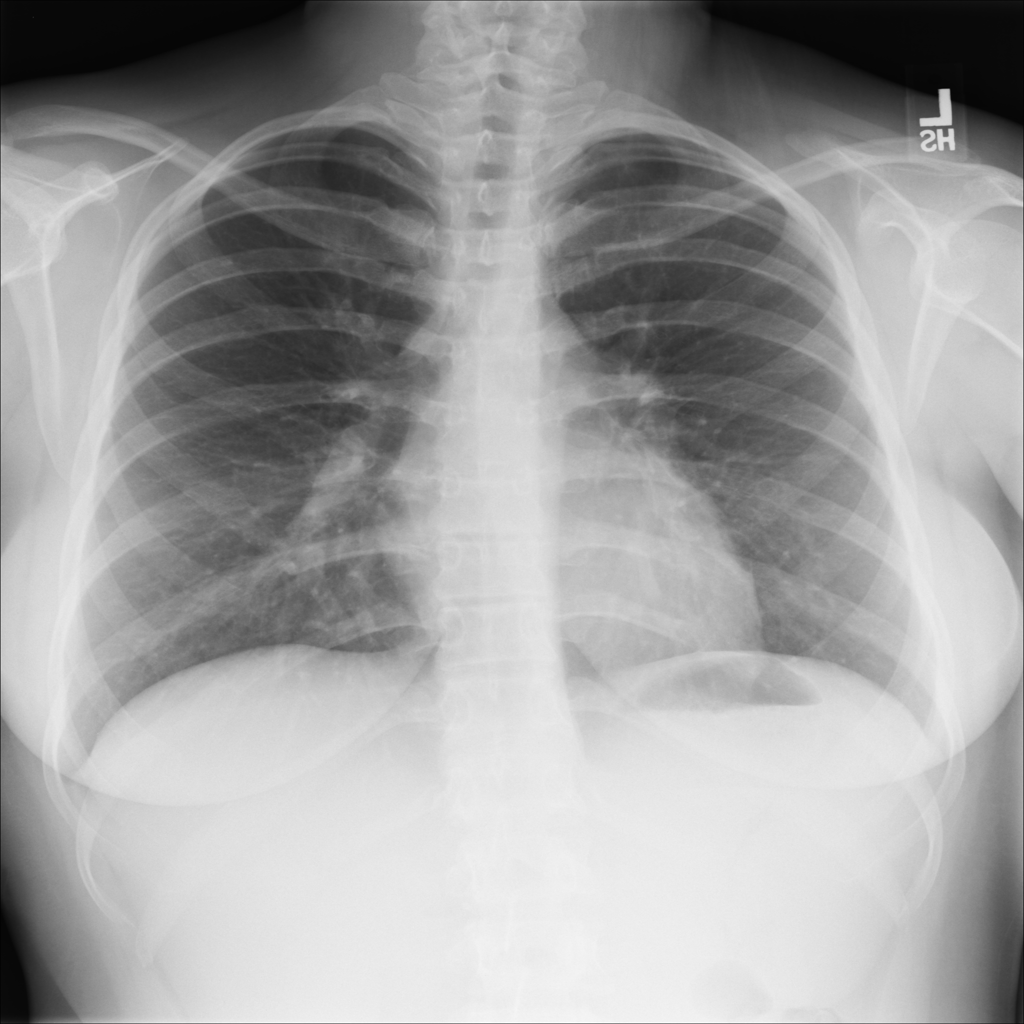

Showing up to 90 reference images for Hernia.

PAT-0ABD · IMG-000Hernia

PAT-0ABD · IMG-000

PA